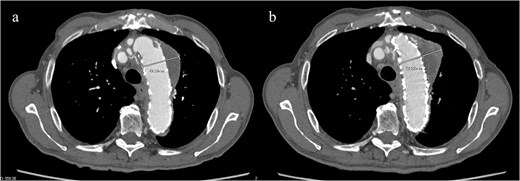

An 83-year-old man presented at our hospital with intermittent hemoptysis. Two years before, he had undergone total arch replacement with FET insertion using a 29 × 120 mm Frozenix J graft (Japan Lifeline, Tokyo, Japan) for a 55 mm aortic arch aneurysm. The Frozenix J graft is a commercially produced open stent graft with an internal skeleton made of nickel-titanium alloy. One year after surgery, postoperative contrast-enhanced computed tomography (CT) showed a reduction in the aneurysm diameter to 49 mm, with no endoleaks (Fig. 1a).

(a) Contrast-enhanced CT 1 year after total arch replacement with FET showing a reduction in aneurysm diameter from 55 mm to 49 mm, with no evidence of endoleak. (b) Contrast-enhanced CT 2 years after total arch replacement with a FET, showing an increase in aneurysm diameter to 56 mm.

CT revealed no endoleak, but the aneurysm had enlarged to a diameter of 56 mm (Fig. 1b). Three-dimensional CT revealed straightening and proximal migration of the FET (Fig. 2). No clear signs of pulmonary parenchymal hemorrhage or findings suggestive of the mass were reported. Laboratory tests indicated mild anemia, with a hemoglobin of 9.7 g/dL and hematocrit of 29.0%. No infectious or inflammatory diseases that could cause hemoptysis were identified.